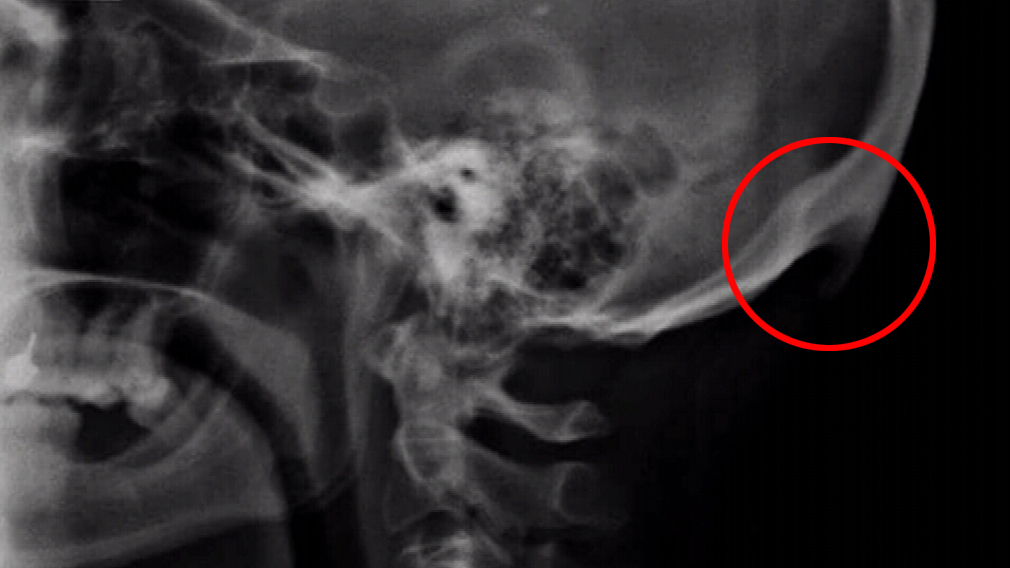

Young people are 'growing HORNS on their skulls' due to excessive Excessive Horn Use Similar incidents in the past have led to court decisions in. relationships between driver awareness of their own horn use and its mode suggested that drivers who did not usually honk. the issue of excessive horn honking is not a new one. Remember to use your horn in emergency situations, as a warning signal, and to communicate with. Excessive Horn Use.